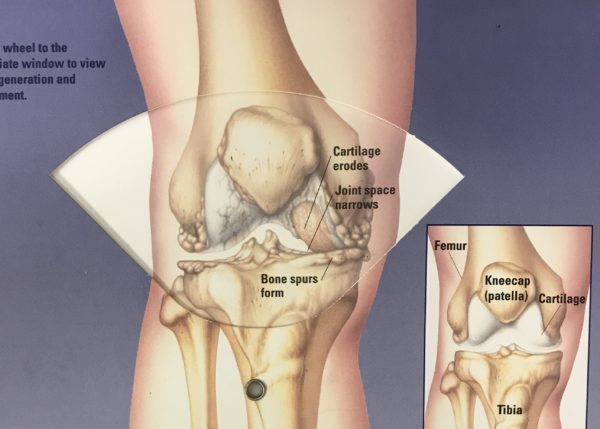

Image courtesy of Sanofi-Aventis

Clinical symptoms include joint pain associated with injury, overuse or advancing age. Two general features include loss of articular cartilage (the “joint space” seen on weight-bearing X-rays) and formation of bone spurs. Bone spurs are a secondary reaction to osteoarthritis and are usually not the cause of pain. Patients often ask if the bone spurs can be removed, but if removal is done without addressing the cause of arthritis, they would simply grow back.